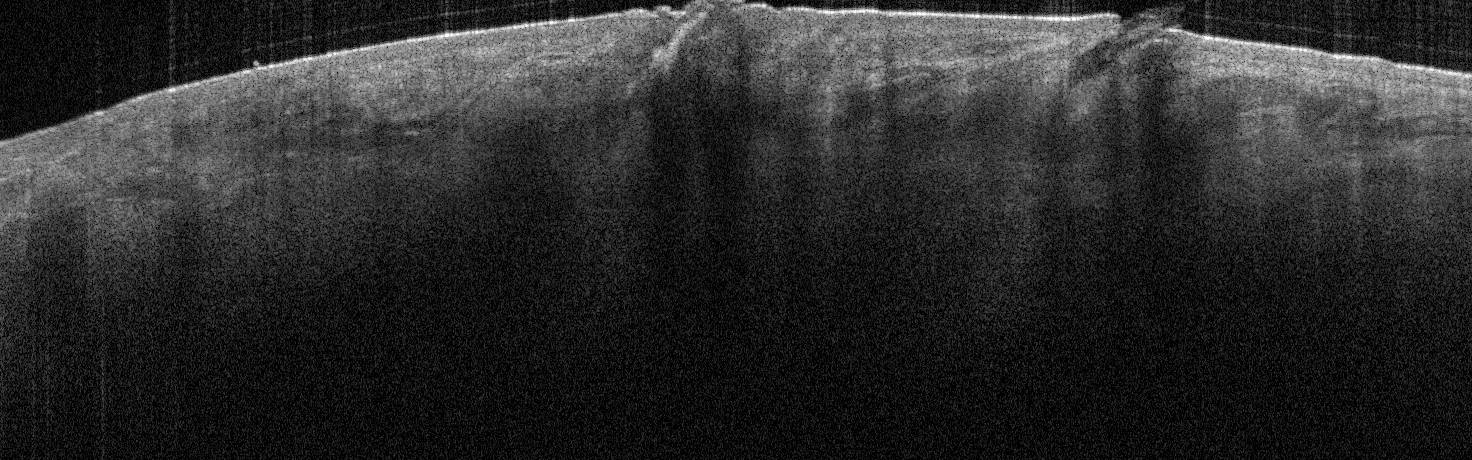

VA34: Right Temple, Actinic Keratosis, Hypotrophic, Focally reaching the base.

- White arrow denotes hair follicle